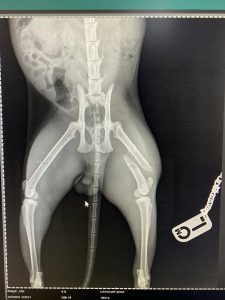

- Liječenje prijeloma kostiju, uključujući intraartikularne frakture

- Liječenje luksacije patele(Luxatio Patellae) Trohleoplastika i TTT(eng. Tibial Tuberosity Transposition)

- Korektivne osteotomije za ispravljanje deformiteta

- Liječenje rupture prednjeg križnog ligamenta koljena TPLO (eng. Tibial Plateau Leveling Osteotomy)